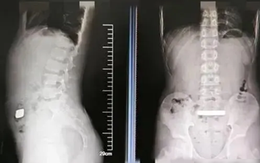

Mới đây, một cậu bé 11 tuổi ở Trung Quốc đã vô tình nuốt phải một thỏi vàng nặng 100 gam khi đang chơi ở nhà.